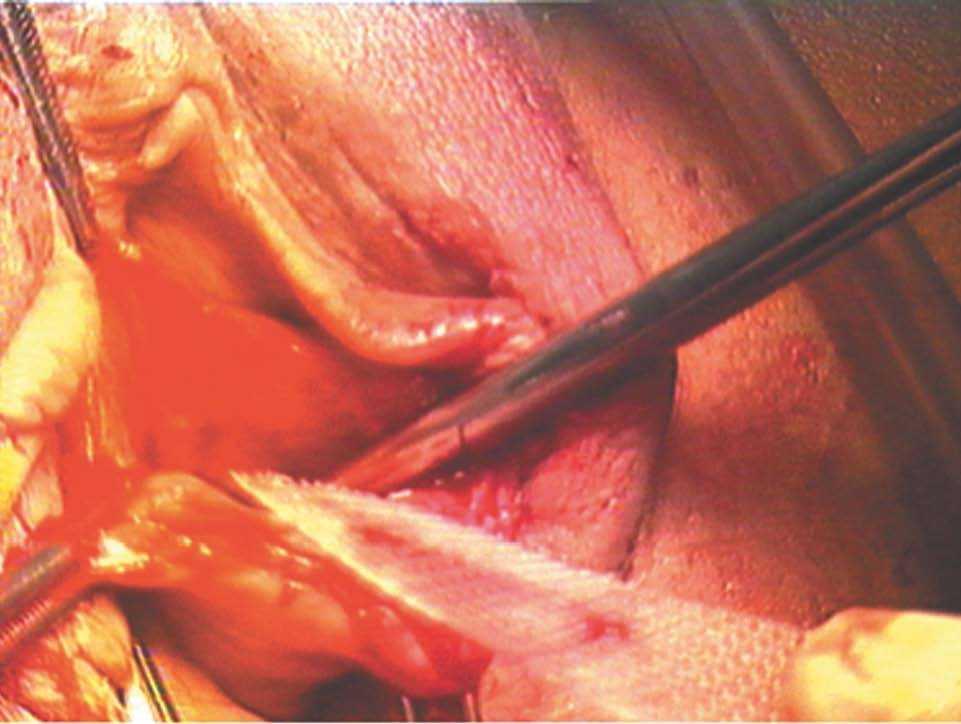

-- Paso primero. Disección del saco herniario de la cúpula vaginal y apertura de ésta (fig. 1).

Figura 1.Detalle del saco herniario de la cúpula vaginal.